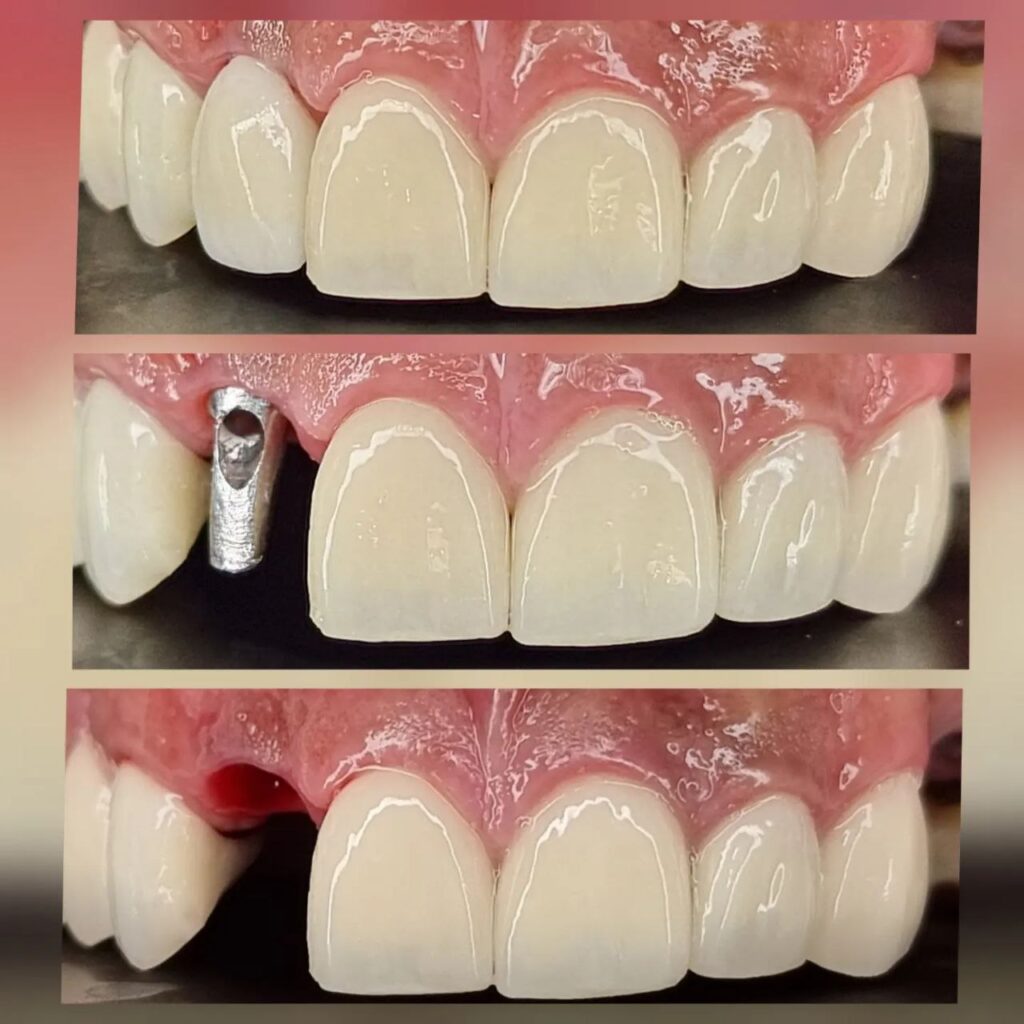

کاشت ایمپلنت دندان

اطمینان حاصل کردن از اینکه دندانهایتان به نحوی زیبا و طبیعی جایگزین شدهاند، از اهمیت بسیاری برخوردار است. ایمپلنت دندان به عنوان یک روش درمانی دائمی در دندانپزشکی شناخته میشود که حاصل آن، یک دندان زیبا و طبیعی در دهان شما خواهد بود.

هرچند که این روش درمانی هزینهی بیشتری نسبت به روشهای دیگر دارد، اما ارزش زیبایی که ایجاد میکند، قابل انکار نیست. ایمپلنتها به قدری شبیه به دندانهای طبیعی هستند که به سختی میتوان آنها را از دیگر دندانها تشخیص داد.